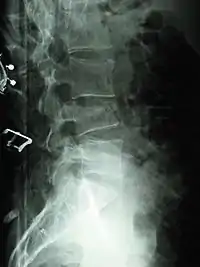

Compression fracture of the fourth lumbar vertebra post falling from a height.